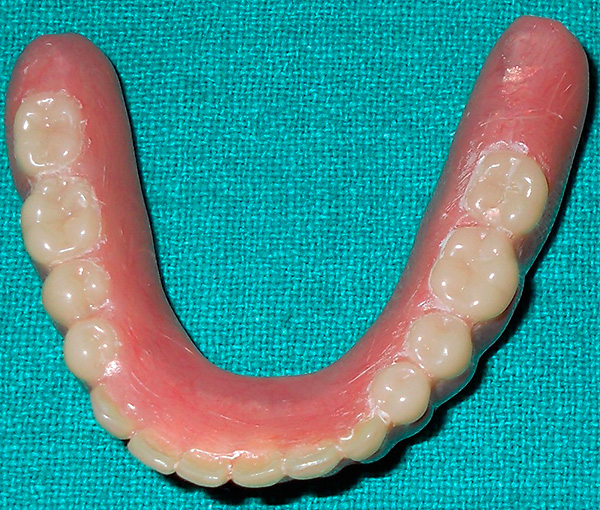

O último estágio do implante basal é a prótese. Após a instalação dos implantes basais, a prótese é geralmente colocada por 2-3 dias - para criar a carga primária necessária. A prótese é feita com moldes removidos da mandíbula do paciente. Ao mesmo tempo, todos os implantes instalados são impressos na impressão, cuja relação espacial já é estudada pelo técnico em odontologia nos modelos obtidos, que faz a prótese necessária no laboratório odontológico (ao mesmo tempo, são levados em consideração os dados do modelo de computador criado na fase preliminar).

As próteses imediatas (imediatas) desempenham um papel muito importante em todo o processo de tratamento.

Primeiramente, a prótese transfere imediatamente a carga mastigatória para os implantes e, através deles, para o tecido ósseo, devido ao qual processos naturais são ativados nela, e a regeneração prossegue o mais rápido possível. Simplificando, o osso é restaurado rapidamente em muitos aspectos, devido ao fato de o paciente poder mastigar alimentos alguns dias após o implante basal.

Em segundo lugar, a prótese conecta todos os implantes instalados em um único design. Se um implante estiver muito carregado, ele será deslocado sob carga. Porém, devido ao fato de a estrutura da prótese unir todas as raízes artificiais, elas ficam imóveis e calmamente se enraízam no tecido ósseo, apesar da presença de intensa carga mastigatória.

Em terceiro lugar, a prótese permite que o paciente se sinta pleno - a estética e a possibilidade de nutrição são restauradas com implante basal quase que imediatamente.

No entanto, há um ponto muito importante (que alguns podem considerar um sinal de menos). Embora após a instalação dos implantes a prótese seja fixa permanente, não removível, mas ainda assim seja uma estrutura temporária. Isso significa que você precisa usá-lo por pelo menos seis meses e, na prática - até 3-4 anos, até as coroas plásticas falharem e perderem a aparência. Após a prótese, você terá que substituí-la por uma permanente - ou seja, uma que permaneceu inativa por décadas.